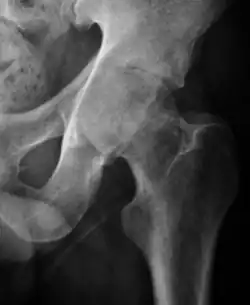

Projectional radiography ("X-ray") is the first imaging technique of choice in hip pain, not only in older people with suspected osteoarthritis but also in young people without any such suspicion. In this case plain radiography allows categorization as normal hip or dysplastic hip, or with impingement signs, pincer, cam, or a combination of both.[1]

X-Ray

Projectional radiography ("X-ray") is currently useful not only in older people in whom osteoarthritis of the hip is suspected but also in younger people without osteoarthritis, who are being evaluated for femoroacetabular impingement (FAI) or hip dysplasia.[1]

Plain radiography allows us to categorize the hip as normal or dysplastic or with impingement signs (pincer, cam, or a combination of both). Besides these, pathologic processes like osteoarthritis, inflammatory diseases, infection, or tumors can also be identified (Figure 1).[1]

- Osteoarthritis

In adults, one of the main indications for radiographs is the detection of osteoarthritic changes (Figure 1(e)). Nevertheless, radiographs usually detect advanced osteoarthritis that can be graded according to the Tönnis classifications. The grading system ranges from 0 to 3, where 0 shows no sign of osteoarthritis. Intermediate grade 1 shows mild sclerosis of the head and acetabulum, slight joint space narrowing, and marginal osteophyte lipping. Grade 2 presents with small cysts in the femoral head or acetabulum, moderate joint space narrowing, and moderate loss of sphericity of the femoral head. Grade 3 is the severest form of osteoarthritis, which manifests as severe narrowing of the joint space, large subchondral cyst with productive bone changes that may lead to deformity of the bone components of the joint, while secondary osteoarthritis due to calcium pyrophosphate deposition can be diagnosed when calcification of hyaline cartilage and fibrocartilage is detected.[1]

There are other pathological conditions that can affect the hip joint and radiographs help to make the appropriate diagnosis. Acute bacterial septic arthritis can be diagnosed by radiographs when a fast regional osteoporosis and destructive monoarticular process develops (Figure 1(f)). In case of tuberculous or brucella arthritis it is manifested as a slow progressive process, and diagnosis may be delayed.[1]